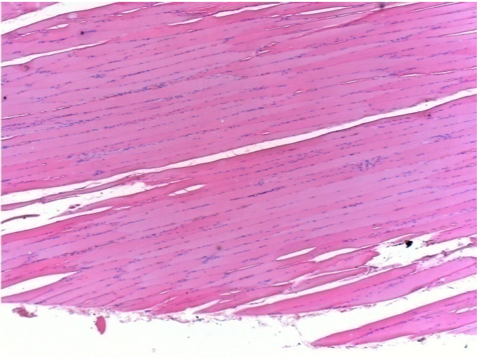

7 months (D210)after Endopeel IM Injection 0.1ml in the right pretibial muscle.

Complete Restitutio ad integrum after 7 months

L :Control 50xD210

R50X-D210